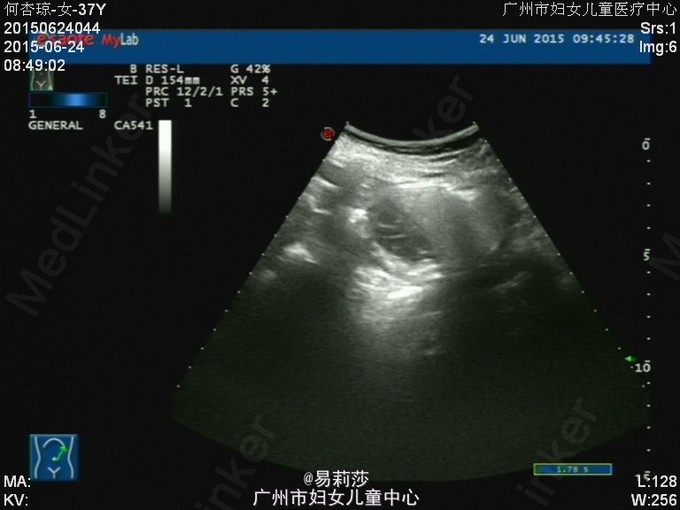

患者何××,女,G0P0,36岁,因“体检发现子宫肌瘤半年”于2015-06-23入院。患者平素月经规则,LMP:2015-06-12。患者于半年前体检时发现子宫肌瘤,未治疗。2月前,患者自觉腹部包块逐渐增大,2015-05-12彩超检查示:子宫前位,后壁见一实性低回声团,范围约125×193×192mm,边界尚清,明显外突,内回声欠均匀,宫腔线隐约可见,双侧附件因肿块遮挡,显示不清,CDFI:上述低回声团内见短棒及条索状血流信号,查血常规示:血红蛋白31g/L,拟“子宫平滑肌瘤”收入我科。入院后查贫血组合示缺铁,予输红细胞悬液6个单位,复查血色素81g/L,患者要求出院,此次再次入院要求手术治疗。查体:T36.2℃,P100次/分,R20次/分,BP132/74mmHg,神清,中度贫血外观,心肺听诊无异常,腹膨隆,宫底达剑突下1cm,无压痛、反跳痛。妇科检查:外阴发育正常,阴毛女性分布;阴道畅,分泌物色白,无异味;宫颈光滑,无肥大,无举痛及着色;宫体前位,增大,宫底达剑突下1cm,质硬,活动差,无压痛;双侧附件未扪及包块及压痛。 辅助检查:2015-06-24彩超检查示:胆囊息肉(胆固醇结晶),副脾,肝、胰、右肾未见明显异常回声,左肾下极异常回声团——畸胎瘤?,考虑来源左侧卵巢可能,与左肾关系密切,巨大子宫肌瘤,左侧卵巢显示不清,请进一步检查。MRI检查示:1.子宫左侧壁巨大实性肿块影,考虑巨大子宫肌瘤可能性大,子宫明显受压;2、左肾下方类圆形病变,考虑畸胎瘤可能性大;3、双侧腹膜后区主动脉、下腔动脉周围见不规则囊状影,考虑淋巴管扩张可能;4、盆腔少量积液。